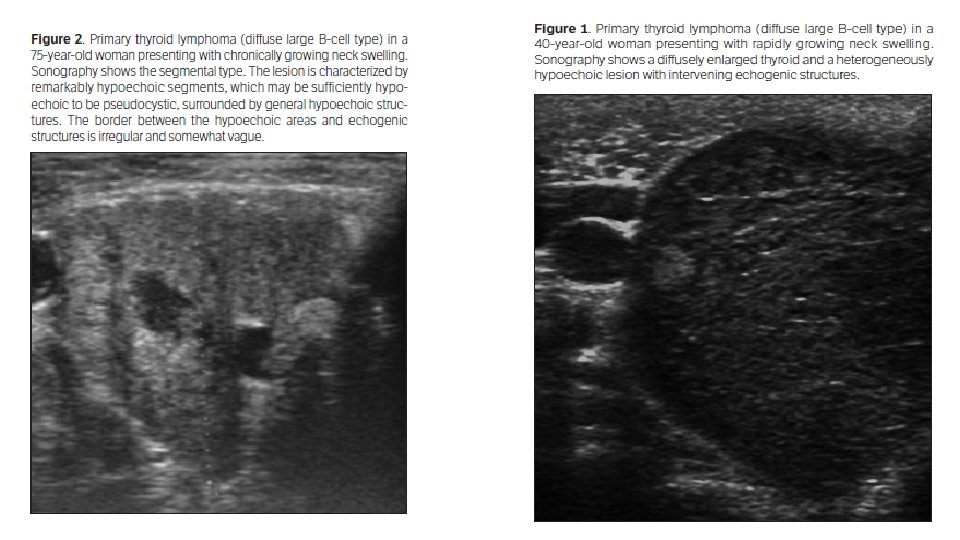

ØWe included 13 consecutive patients with pathologically proven primary thyroid lymphoma at Xiangya Hospital from 2007 to 2013 ØAnother 27 patients were randomly chosen as controls who had pathologically proven nodular goiter at our hospital from 2012 to 2013

Comparison of Clinical and Sonographic Features Between Primary Thyroid Lymphoma and Nodular Goiter